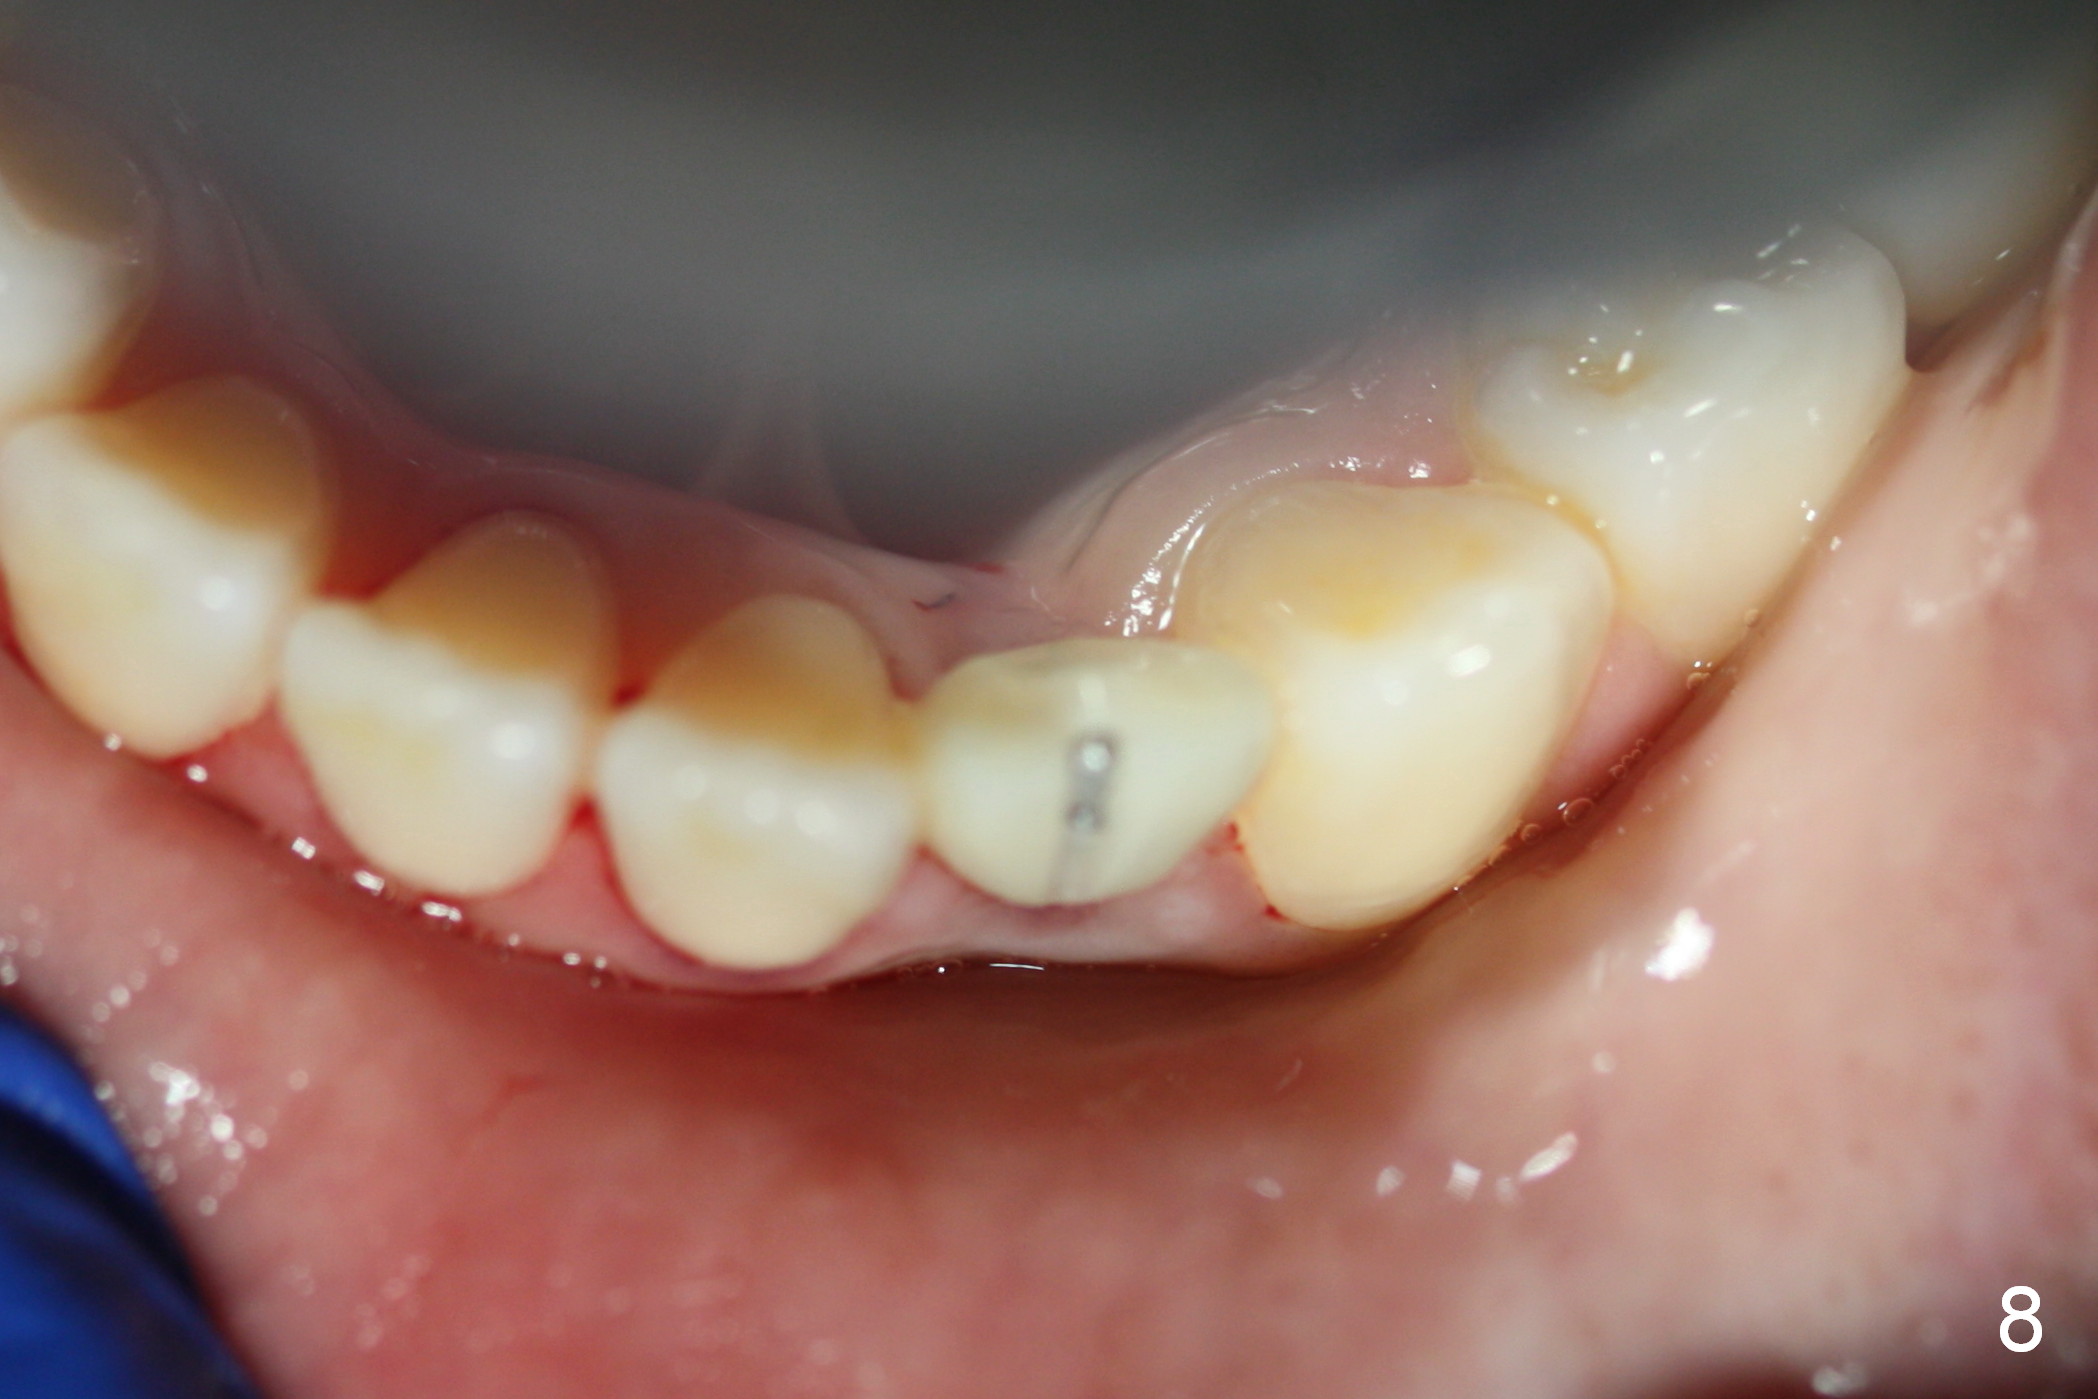

Make the crown a little more bulky buccally than the

old crown (Fig.8). The implant

has been placed for 2 years 8 months.

It has already osteointegrated.

The buccal surface of the abutment has been further reduced prior to final impression (the previous cast is enclosed in the case).